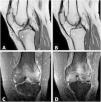

Transient osteoporosis of pregnancy is a rare entity, often underdiagnosed, because it presents mechanical pain that is also characteristic of the adaptive changes in pregnancy. It is more frequent in previously healthy women during the third trimester of pregnancy.8,9 It can occur in 2 forms: systemic and regional. The systemic form mainly affects the trabecular bone and, in particular, the spine. Its prevalence is unknown, since some of its predominant clinical manifestations, such as low back pain, are typical in the course of a normal gestation, due to the mechanical overload inherent to pregnancy.10 The regional form, which predominates in our series of cases, usually settles on load-bearing joints, with the most frequent location in the hip, followed by the knee. Bilateral involvement is more exceptional. Nevertheless, in our case series 50% of the patients had bilateral gonalgia, 25% migratory coxalgia and another 25% postpartum right coxalgia (Figs. 1–4).

MRI is the imaging test indicated to demonstrate the characteristic edema of the bone marrow of the affected joint, as it is sensitive enough to detect it in the first 48¿;hours from the onset of symptoms.13 It shows increased signal intensity in fat-suppressed T2-weighted or STIR images and decreased signal intensity in T1-weighted images,6,8 as observed in the images presented in our case series.